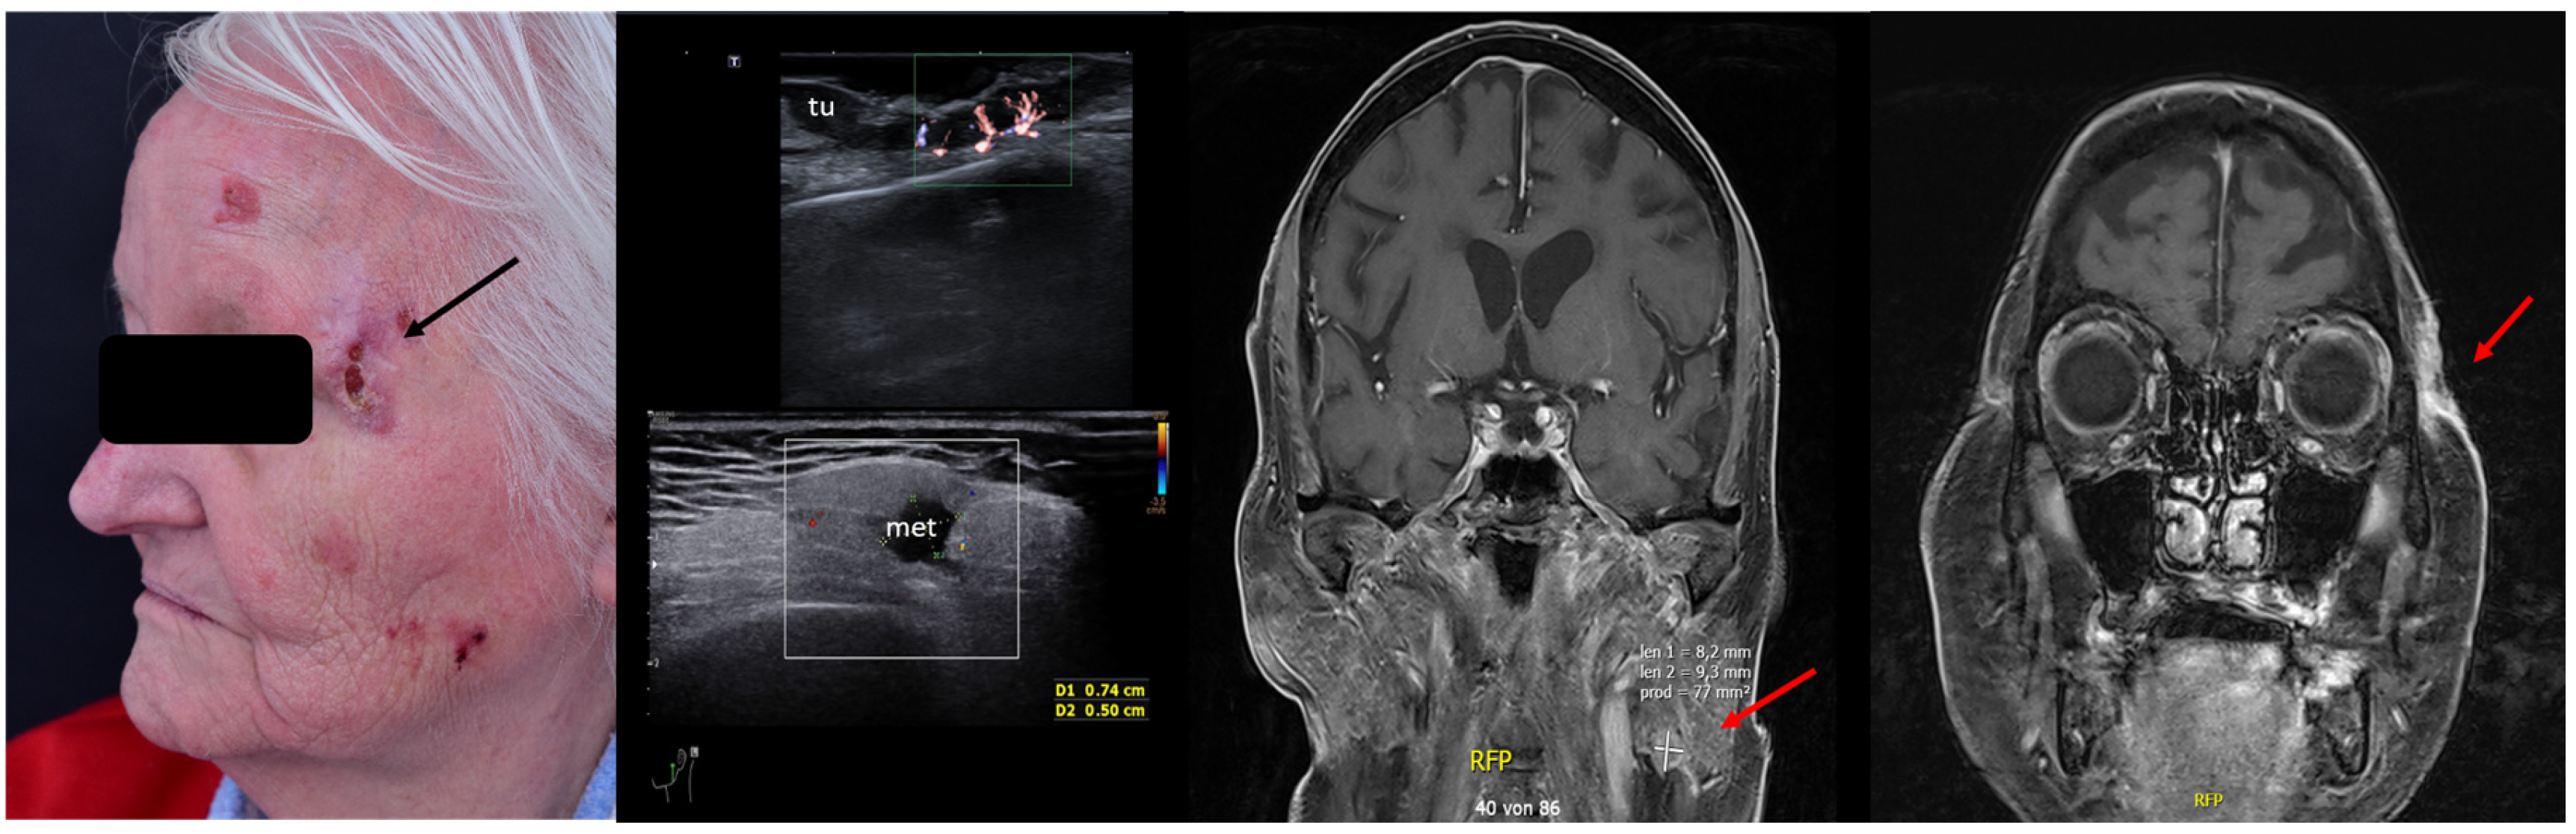

2. Enhancement of Diagnostic Accuracy, Avoidance of Misdiagnosis, Early Identification of Local Relapse

10. Avoidance of Unnecessary Surgeries due to Patient Up-Staging